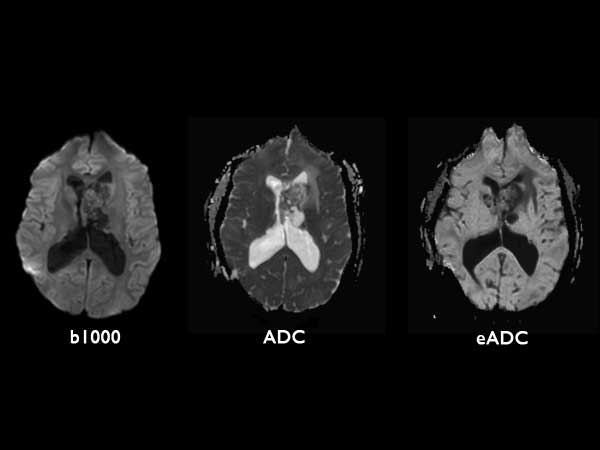

Axial Diffusion